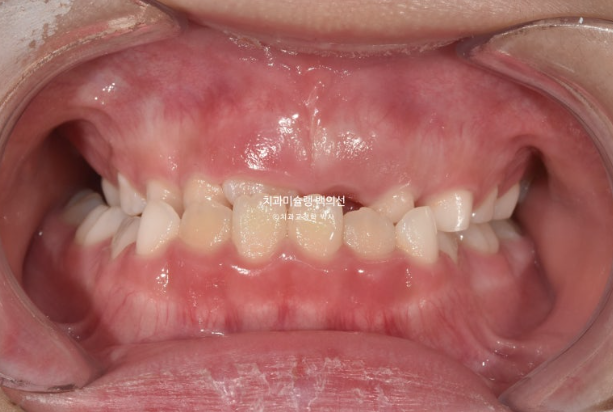

2022년 8월 내원한 어린이 입니다.

앞니 반대교합과 비대칭 치료를 위해 오셨습니다.

앞니 뿐 아니라 송곳니, 일부 어금니까지 거꾸로 물리는 상황입니다.

앞니 반대교합은 프리올소와 같은 장치로 간단하게 넘겨줄 수 있지만 더 큰 문제는 비대칭입니다.

아래앞니와 함께 아래턱이 우측으로 돌아가 있습니다.